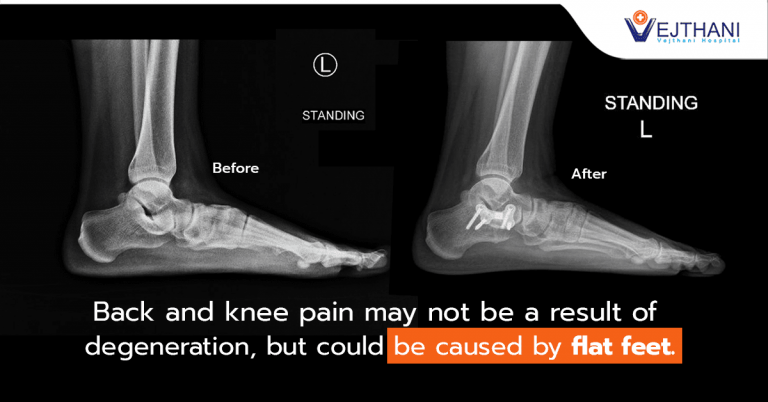

Flat Feet may Cause Back and Knee Pain

The reason is because the entire sole of the foot completely contacts or in close-contact with the ground, causing high pressure in the sole of the foot and ankle. Therefore, people with flat feet are at higher risk of having pain in their feet and shins. Moreover, people with flat feet also put high pressure on their knees which is also one of the causes of pain in their knees and back.